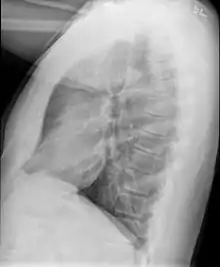

Causes include breathing in toxic fumes, respiratory infections, connective tissue disorder or complications following a bone marrow or heart-lung transplant.[1] Symptoms may not occur until two to eight weeks following toxic exposure or infection.[1] The underlying mechanism involves inflammation that results in scar tissue formation.[1] Diagnosis is by CT scan, pulmonary function tests or lung biopsy.[1] A chest X-ray is often normal.[4]

A form of constrictive bronchiolitis is starting to present in Iraq and Afghanistan veterans. It has been attributed to veterans being exposed to trash burn pits. Veterans present with shortness of breath and other asthma-like symptoms. The only way to diagnose this condition is by doing a lung biopsy as chest X-rays and CT scans come back as normal. The government still denies that there is any correlation between burn pits and health problems but the government has started an "Airborne Hazards and Open Burn Pit Registry" to begin tracking the health of veterans who were exposed to burn pits to see if there is a connection.[35][36]

Early in the disease chest radiography is typically normal but may show hyperinflation.[6] As the disease progresses a reticular pattern with thickening of airway walls may be present.[4][6] HRCT can also show air trapping when the person being scanned breathes out completely; it can also show thickening in the airway and haziness in the lungs.[11] A common finding on HRCT is patchy areas of decreased lung density, signifying reduced vascular caliber and air trapping.[6] This pattern is often described as a "mosaic pattern", and may indicate obliterative bronchiolitis.[6]